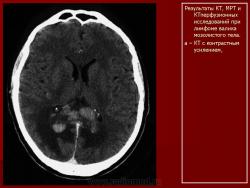

Лимфомы головного мозга.